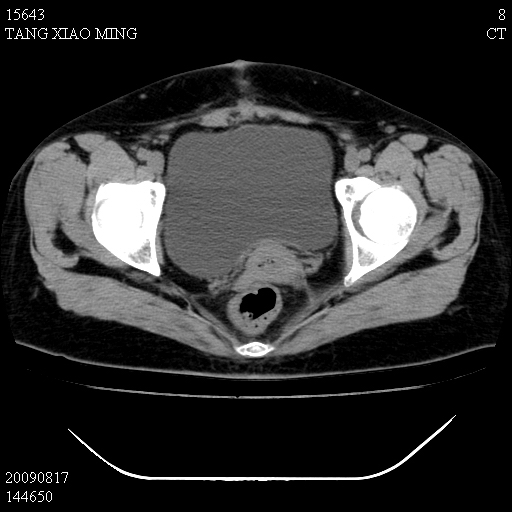

标题: CT21692:盆腔病变

女,33岁,右下腹痛2年余,既往宫外孕病史,如在我院手术,结果下周公布,

可能的诊断。1子宫内膜异位【子宫腺肌症并右卵巢巧克力囊肿】;2 右卵巢囊腺瘤。子宫肌瘤

1)考虑卵巢巧克力囊肿,不排除卵巢囊腺瘤。2)子宫肌瘤可能。

卵巢囊腺瘤,子宫肌瘤,直肠壁厚,不除外占位.